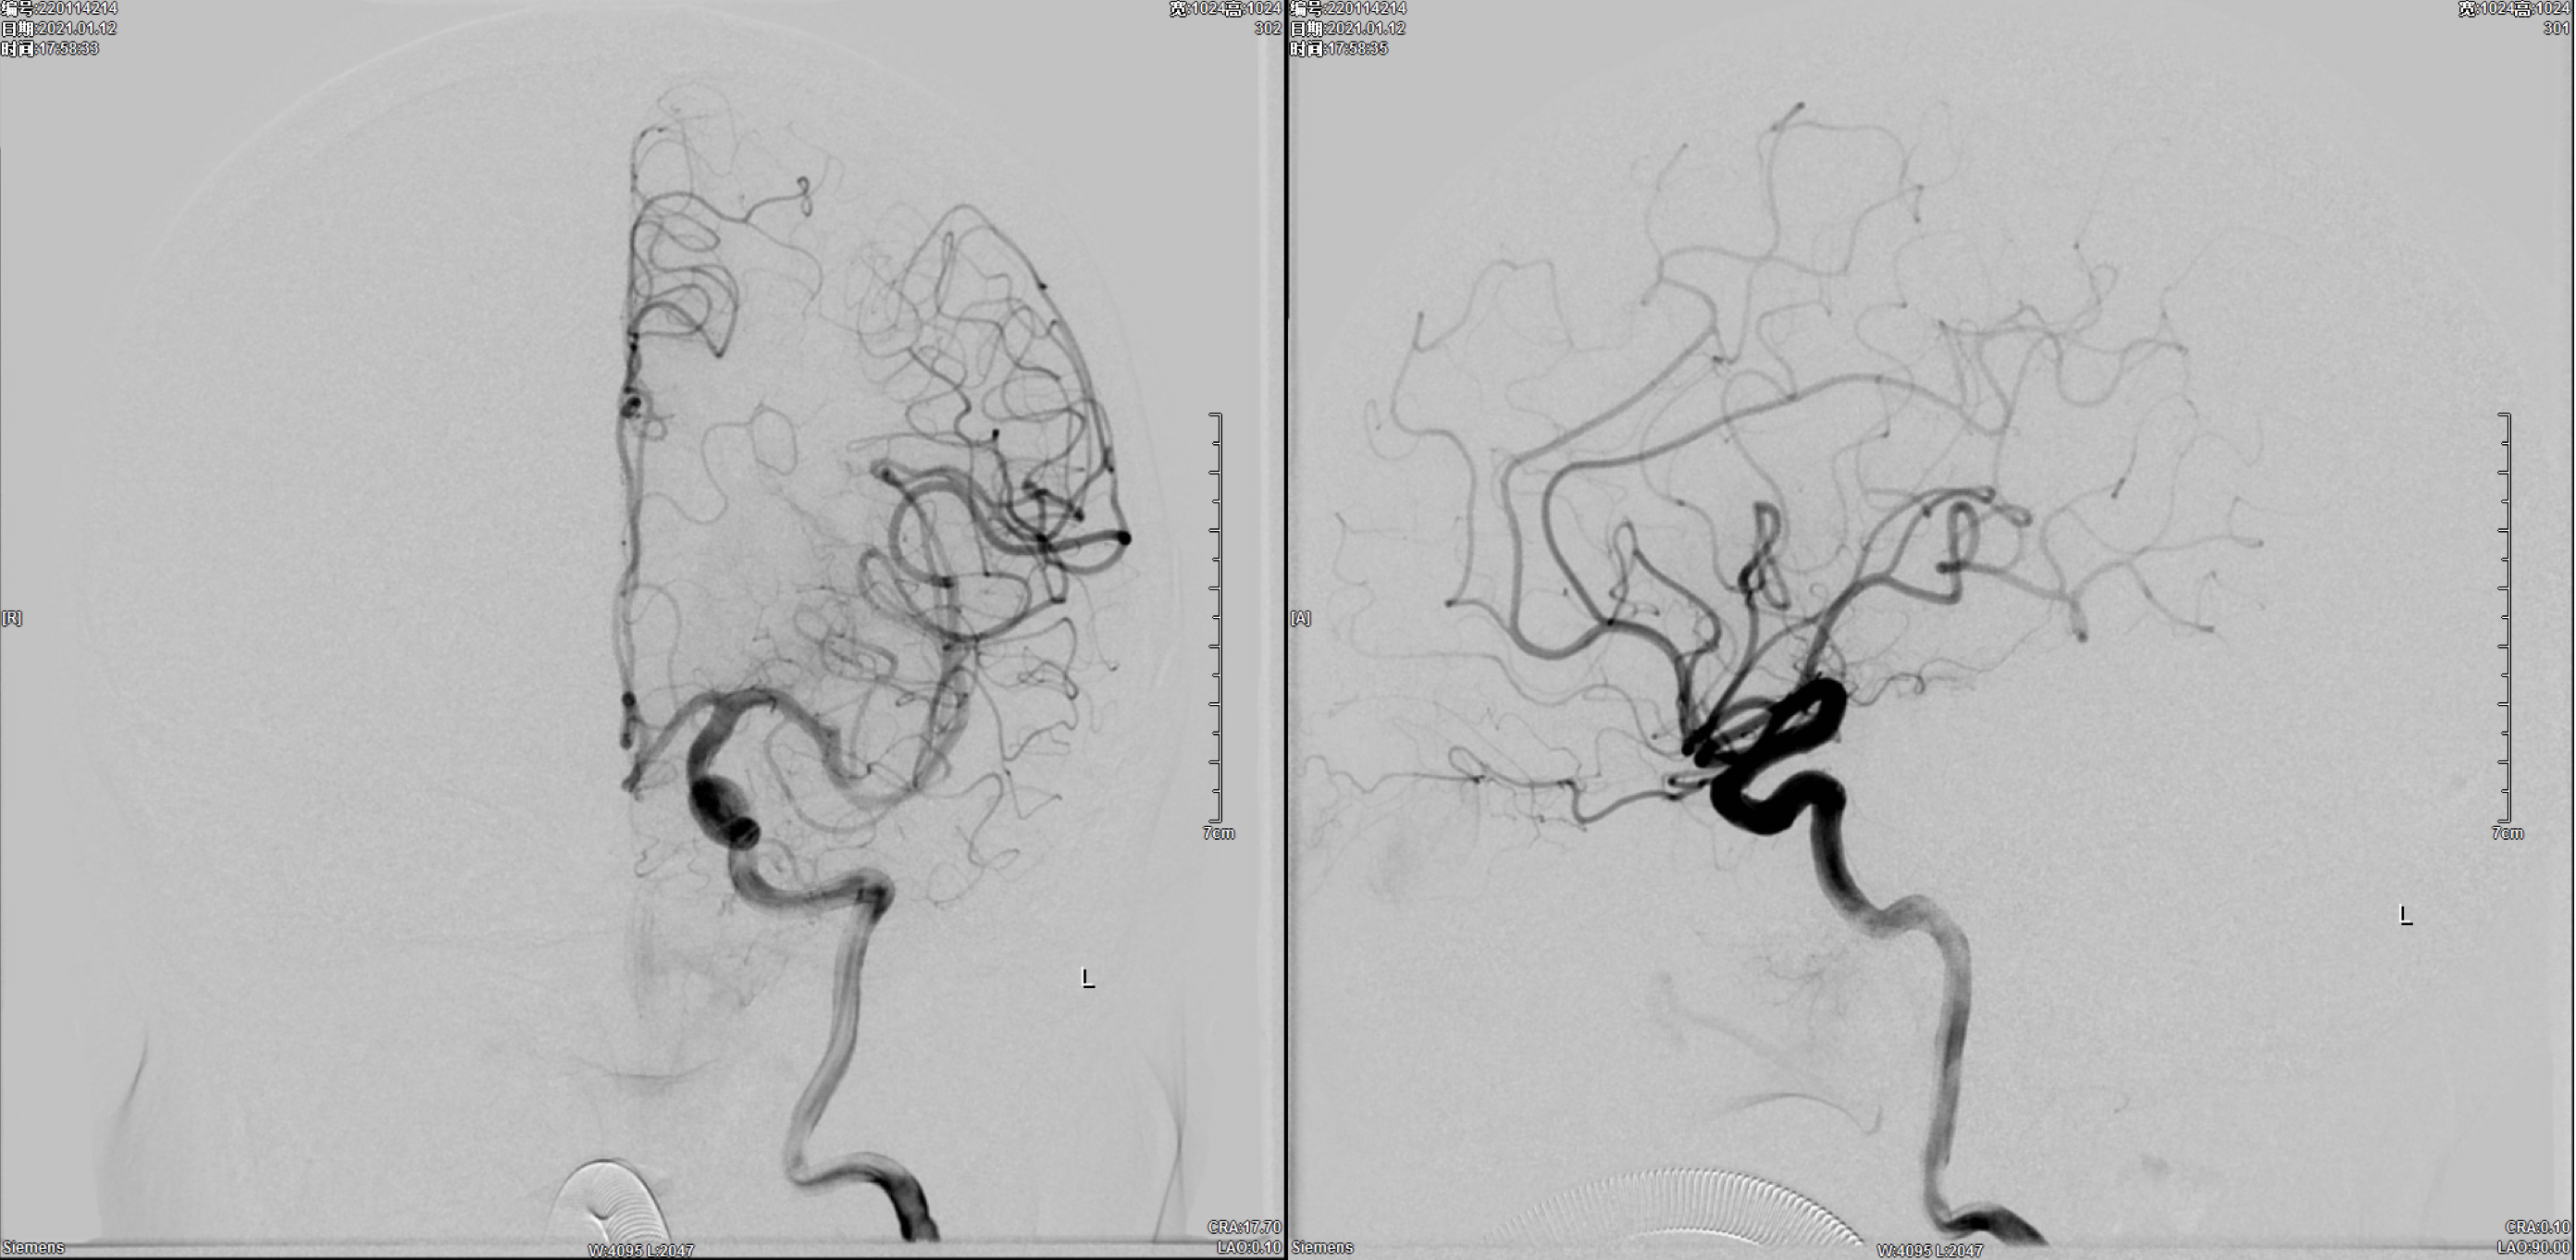

左侧颈内动脉正侧位造影:未见明显异常!

左侧颈动脉正侧位造影:未见明显异常!

右侧颈动脉正侧位造影:右椎动脉发育纤细!

右侧颈内动脉正侧位造影:后交通动脉瘤,后交通动脉发育粗大!

右颈内动脉三维重建:粗大的后交通动脉自近心端瘤颈发出!闭塞后交通动脉可能会出现临床症状,似乎可以通过支架的推“灯笼”保护,但瘤体较大,尽可能栓塞完全,故考虑瘤腔内双微导管分区填塞!